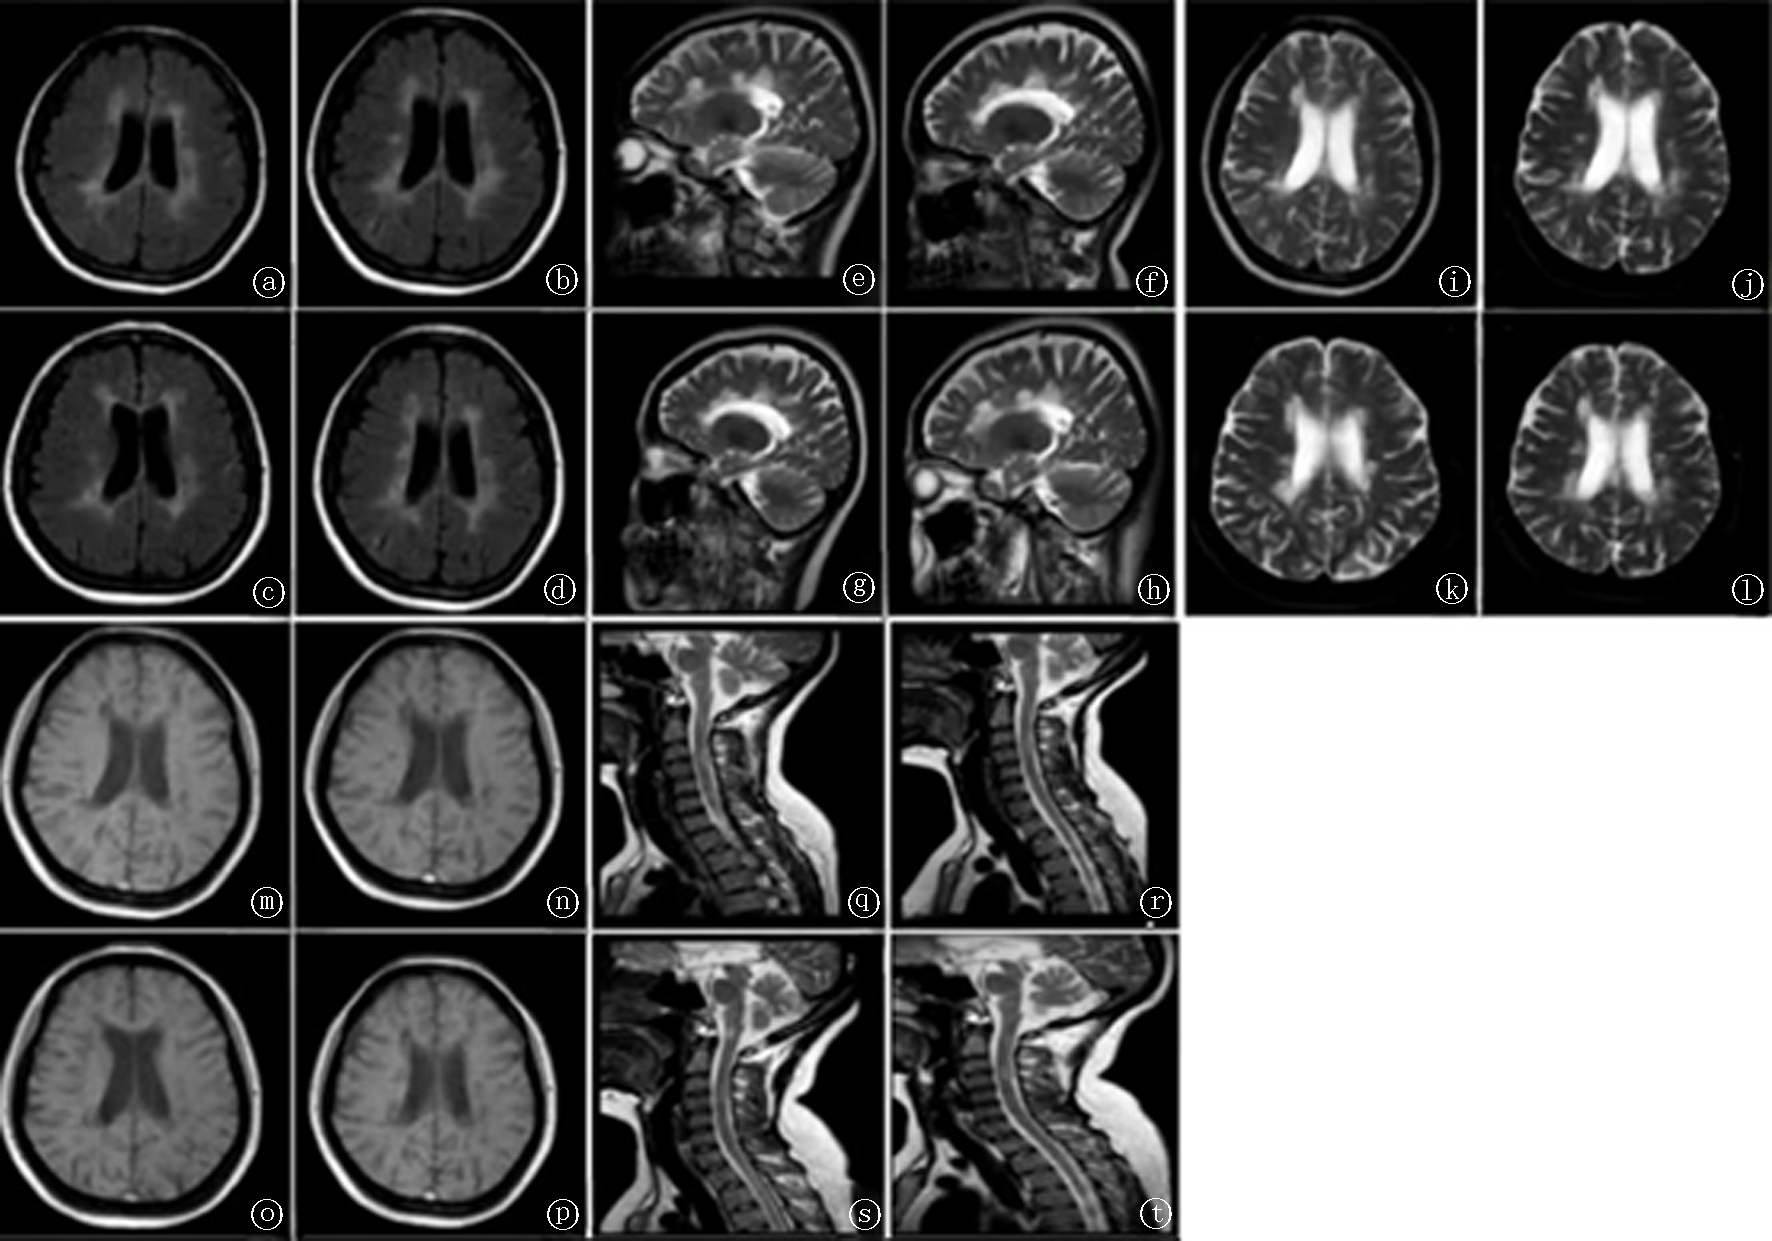

目的 探讨复发缓解型多发性硬化的临床特征、诊断及经验分享。方法 回顾性分析复发缓解型多发性硬化1例,并复习相关文献。结果 患者青年女性,主因左下肢无力16年,加重2月入院,发病前有复发缓解病史,合并银屑病病史,给予甲泼尼龙琥珀酸钠冲击治疗、口服吗替麦考酚酯胶囊等综合治疗后患者病情好转。出院后半年电话随访,患者病情平稳。结论 结合病史、症状、体征及影像学检查综合分析、早期诊断是治疗复发缓解型多发性硬化的关键。

Objective To summarize the clinical characteristics, diagnostic approach, and clinical experience in a case of relapsing-remitting multiple sclerosis (RRMS). Methods We retrospectively analyzed one case of RRMS and reviewed the relevant literature. Results The patient was a young female with a 16-year history of left lower-limb weakness, who was admitted after a 2-month aggravation of symptoms. Her history included relapsing-remitting disease activity and comorbid psoriasis. She received intravenous methylprednisolone sodium succinate pulse therapy along with oral mycophenolate mofetil capsules and other comprehensive treatments, after which her condition improved. Telephone follow-up six months after discharge indicated stable clinical status. Conclusion Timely, early diagnosis founded on an integrated assessment of medical history, clinical signs and symptoms, and imaging is crucial for the management of RRMS.